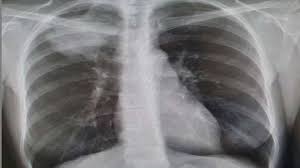

How Do You Know If You Have Cancer In Your Lungs : Lung Cancer Signs Symptoms And Complications - See your doctor if you have shortness of breath that concerns you.. A fracture in the bone after a small injury can also sign that cancer in the lungs has spread. Screening is looking for cancer before you have any symptoms, which can help find cancer at an early stage when it may be easier to treat. How do you know if you have cancer in your lungs. Symptoms of lung cancer are cough, chest pain, and trouble breathing. A ct scan (computed tomography scan) alone may not be enough to confirm or rule out lung cancer.

You don't need to necessarily be worried about lung cancer. If you do not have an explanation for your pain, however, it's important to see your doctor. Your doctor may recommend imaging tests, sputum cytology or a tissue sample, called a biopsy. Signs and symptoms of lung cancer may include: If you have pulmonary edema, they fill with fluid instead.

What Are The Chances A Lung Nodule Or Spot Is Cancer Health Essentials From Cleveland Clinic from 2rdnmg1qbg403gumla1v9i2h-wpengine.netdna-ssl.com A new cough in a smoker or a former smoker should raise concern for lung cancer. Frequent infections can also be a red flag pointing at lung cancer. When you take a breath, your lungs should fill with air. Your doctor may recommend imaging tests, sputum cytology or a tissue sample, called a biopsy. (see if you're a candidate at the ala's. When that happens, oxygen from the air can't get from your lungs into your blood,. And if you have sensitive lungs, it's not unusual for your cough to linger even after the runny nose and other symptoms go away. As the cancer develops, these.

Frequent infections can also be a red flag pointing at lung cancer. 18 years experience hematology and oncology. Does anyone knows a good lung cancer site? Metastatic cancers take the name of the primary cancer instead of the name of the organ they've spread to. A fracture in the bone after a small injury can also sign that cancer in the lungs has spread. And if you have sensitive lungs, it's not unusual for your cough to linger even after the runny nose and other symptoms go away. When you take a breath, your lungs should fill with air. Check nccn or the american cancer society web sites, they are both full of information, and the information comes from good legitimate. A cough that doesn't go away (often worse at night) Signs and symptoms of lung cancer typically occur when the disease is advanced. Metastatic cancer to the lungs means that cancer from another region of the body has spread to the lungs. Pain is the way in which our bodies tell us something is wrong. Your windpipe divides into two tubes called the bronchi, which lead to your left and right lungs.

If you have pulmonary edema, they fill with fluid instead. Advanced lung cancer can spread to the bones, causing metastatic bone cancer. The most common signs and symptoms of lung cancer are cough, shortness of breath and weight loss, joshua sabari, a doctor and lung cancer expert at nyu langone's perlmutter cancer center, tells. Your windpipe divides into two tubes called the bronchi, which lead to your left and right lungs. Symptoms of lung cancer are cough, chest pain, and trouble breathing.

Common causes of malignant pleural effusion are lymphoma and cancers of the breast, lung, and ovary. Symptoms of lung cancer are cough, chest pain, and trouble breathing. Pain is the way in which our bodies tell us something is wrong. The most common signs and symptoms of lung cancer are cough, shortness of breath and weight loss, joshua sabari, a doctor and lung cancer expert at nyu langone's perlmutter cancer center, tells. Signs and symptoms of lung cancer typically occur when the disease is advanced. When that happens, oxygen from the air can't get from your lungs into your blood,. How do you know if you have cancer in your lungs. And the cancer can interrupt with the balance of osteoclasts and osteoblasts. Cancer cells in the lung can sometimes travel to the brain and grow there. The early symptoms of lung cancer may be a slight cough or shortness of breath, depending on which part of the lung is affected, according to the cancer center. The chance that shoulder pain is related to lung cancer is usually small. Frequent infections can also be a red flag pointing at lung cancer. Your windpipe divides into two tubes called the bronchi, which lead to your left and right lungs.

Metastatic cancers take the name of the primary cancer instead of the name of the organ they've spread to. If signs point to lung cancer, more tests will be done. Symptoms of lung cancer are cough, chest pain, and trouble breathing. A ct scan (computed tomography scan) alone may not be enough to confirm or rule out lung cancer. Signs and symptoms of lung cancer may include:

How Long Do You Live After Being Diagnosed With Lung Cancer Lung Cancer Lawsuit Lawyers Pintas Mullins Law Firm from www.pintas.com If a lung cancer tumor is blocking a major airway, it could cause shortness of breath. A fracture in the bone after a small injury can also sign that cancer in the lungs has spread. First, you may be comforted to know that, while lung nodules may be an indicator of lung cancer, benign nodules are common. A ct scan (computed tomography scan) alone may not be enough to confirm or rule out lung cancer. A new cough that doesn't go away coughing up blood, even a small amount Another term for metastatic cancer to the lungs is secondary cancer in the lungs, as the primary cancer is the place in the body where cancer began or originated. If you do not have an explanation for your pain, however, it's important to see your doctor. A malignant pleural effusion is treatable.

18 years experience hematology and oncology. Does anyone knows a good lung cancer site? The treatment that you may have depends on your type of primary cancer, where it has spread, treatments you've had in the past, and your general health. Check nccn or the american cancer society web sites, they are both full of information, and the information comes from good legitimate. Signs and symptoms of lung cancer typically occur when the disease is advanced. Cancer cells in the lung can sometimes travel to the brain and grow there. A ct scan (computed tomography scan) alone may not be enough to confirm or rule out lung cancer. If you are experiencing shoulder pain, don't panic. For instance, if you have lung cancer, but it has metastasized to the brain, it would. The doctor will ask you questions about your health and do a physical exam. A new cough in a smoker or a former smoker should raise concern for lung cancer. Sometimes fluid in the lungs can make breathing difficult and this could also be a sign of lung cancer. Signs that warrant an immediate trip to a doctor some common cancer signs that should result in a visit to the emergency room or to a doctor as soon as possible include: